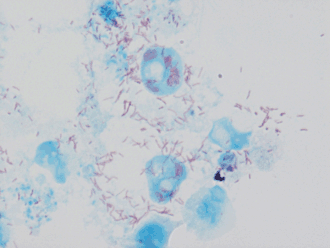

Rickettsia conorii est une bactérie Gram-négative intracellulaire obligatoire.